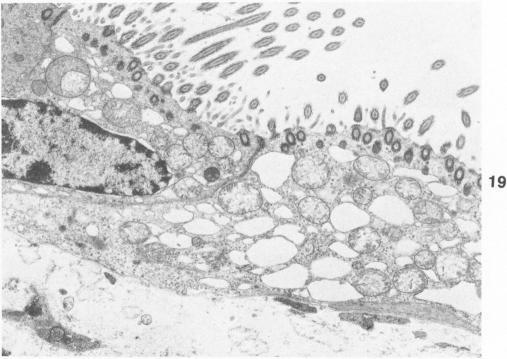

The morphogenesis of pulmonary lesions and associated edema induced by the pulmonary toxicant 3-methylindole (3-MI) was studied by combined light and transmission electron microscopy. Weanling male CD-1 mice received 3-MI dissolved in corn oil by intraperitoneal injection and were studied at intervals from 2 to 360 hours after treatment. Interstitial edema was observed as early as 2 hours and was associated with focal cytoplasmic swelling and membrane alterations in both capillary endothelial cells and Type I alveolar epithelial cells and with sequestration of neutrophils. Cell swelling, cytoplasmic fragmentation, and necrosis of Type I epithelial cells was most severe at 24-48 hours after treatment. Multifocal hypertrophy and hyperplasia of Type II alveolar epithelial cells was observed at 24-96 hours after treatment. Platelet aggregation and aggregates of fibrin were frequently observed in capillaries and small arteries and veins as early as 4 hours and as late as 48 hours after treatment. In airways, the nonciliated bronchiolar epithelial (Clara) cell was the predominant cell affected. Initial lesions in nonciliated cells consisted of loss of microvilli and secretory granules followed by marked swelling of the endoplasmic reticulum and mitochondria. Necrosis of cells lining airways was most pronounced at 24-48 hours after treatment. By 144 hours after administration, pulmonary repair was complete. It is concluded that the mouse is a useful model of 3-MI-induced pulmonary injury and that damage to both Type I alveolar epithelial cells and capillary endothelial cells is important in the pathogenesis of 3-MI-induced pulmonary edema.

通过光学显微镜和透射电子显微镜相结合的方法,研究了肺部毒物3-甲基吲哚(3-MI)诱导的肺部病变及相关水肿的形态发生过程。断奶雄性CD-1小鼠腹腔注射溶于玉米油的3-MI,并在处理后2至360小时内定期进行研究。早在2小时就观察到间质水肿,其与毛细血管内皮细胞和I型肺泡上皮细胞的局灶性细胞质肿胀、膜改变以及中性粒细胞的隔离有关。I型上皮细胞的细胞肿胀、细胞质碎片化和坏死在处理后24至48小时最为严重。在处理后24至96小时观察到II型肺泡上皮细胞的多灶性肥大和增生。早在处理后4小时和晚至48小时,在毛细血管和小动脉及静脉中经常观察到血小板聚集和纤维蛋白聚集体。在气道中,无纤毛细支气管上皮(克拉拉)细胞是受影响的主要细胞。无纤毛细胞的初始病变包括微绒毛和分泌颗粒的丧失,随后是内质网和线粒体的明显肿胀。气道内衬细胞的坏死在处理后24至48小时最为明显。给药后144小时,肺部修复完成。结论是,小鼠是3-MI诱导的肺损伤的有用模型,I型肺泡上皮细胞和毛细血管内皮细胞的损伤在3-MI诱导的肺水肿发病机制中起重要作用。